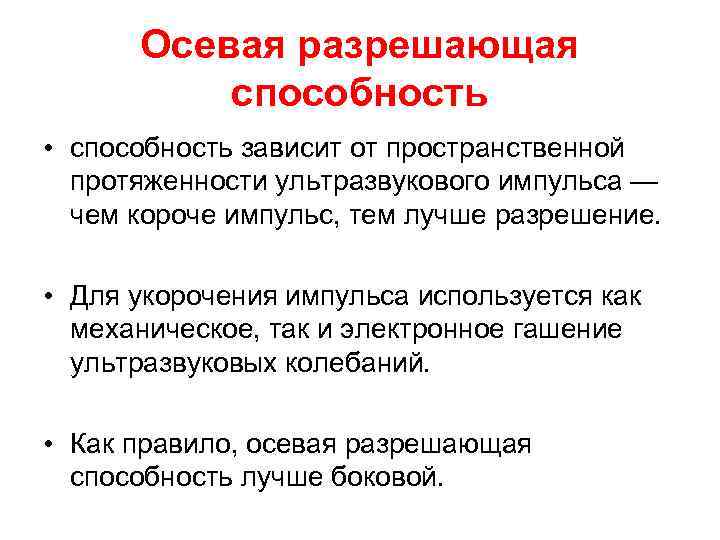

Осевая разрешающая способность • способность зависит от пространственной протяженности ультразвукового импульса — чем короче импульс, тем лучше разрешение. • Для укорочения импульса используется как механическое, так и электронное гашение ультразвуковых колебаний. • Как правило, осевая разрешающая способность лучше боковой.

Осевая разрешающая способность • способность зависит от пространственной протяженности ультразвукового импульса — чем короче импульс, тем лучше разрешение. • Для укорочения импульса используется как механическое, так и электронное гашение ультразвуковых колебаний. • Как правило, осевая разрешающая способность лучше боковой.